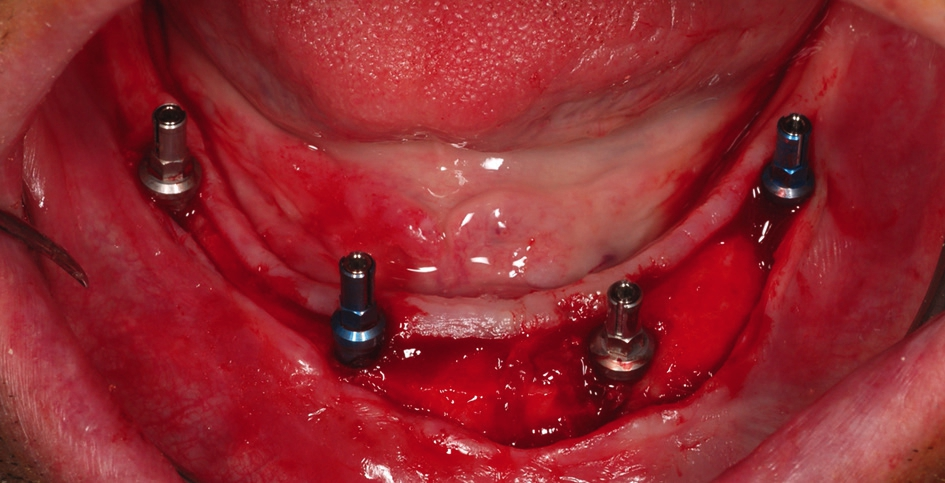

Die Implantatinsertion wurde unter Lokalanästhesie und unter direkter Sicht mit Bildung eines Mukoperiostlappens durchgeführt. Das offene Vorgehen wurde gewählt, da eine fortgeschrittene Resorption des knöchernen Alveolarfortsatzes in oro-vestibulärer Richtung vorlag und auf diese Weise eine sehr gute Beurteilung der Knochenkonturen und der Qualität des Knochens sowie eine Implantatpositionierung unter direkter Sicht ermöglicht wurden [33-35]. Es wurden BEGO Semados® RSX Implantate (BEGO Implant Systems) mit den Standarddurchmessern 3,75 mm (regio 036 und 043) und 4,10 mm (regio 046 und 033) verwendet. Die Implantation erfolgte freihändig nach dem Standardprotokoll des Herstellers. Alle Implantate wurden, mit Ausnahme des Implantats in regio 043, epikrestal am bukkalen Aspekt eingesetzt (Abb. 4). Da der Alveolarkamm sattelförmig gestaltet war, lag der Implantathals bei allen Implantaten approximal jeweils etwa 1,0 mm subkrestal. Das Implantat in regio 043 wurde nach lingual hin ca. 2,0 mm subkrestal inseriert.

Aufgrund des guten vertikalen Knochenangebotes konnten im Eckzahnbereich 11,5 mm lange Implantate und im Seitenzahnbereich Implantate mit der Länge von 10 mm verwendet werden. Dabei war eine Abwinkelung der Implantate im Seitenzahnbereich – wie sonst bei der klassischen All-on-4® Methode üblich – nicht notwendig (Abb. 5).